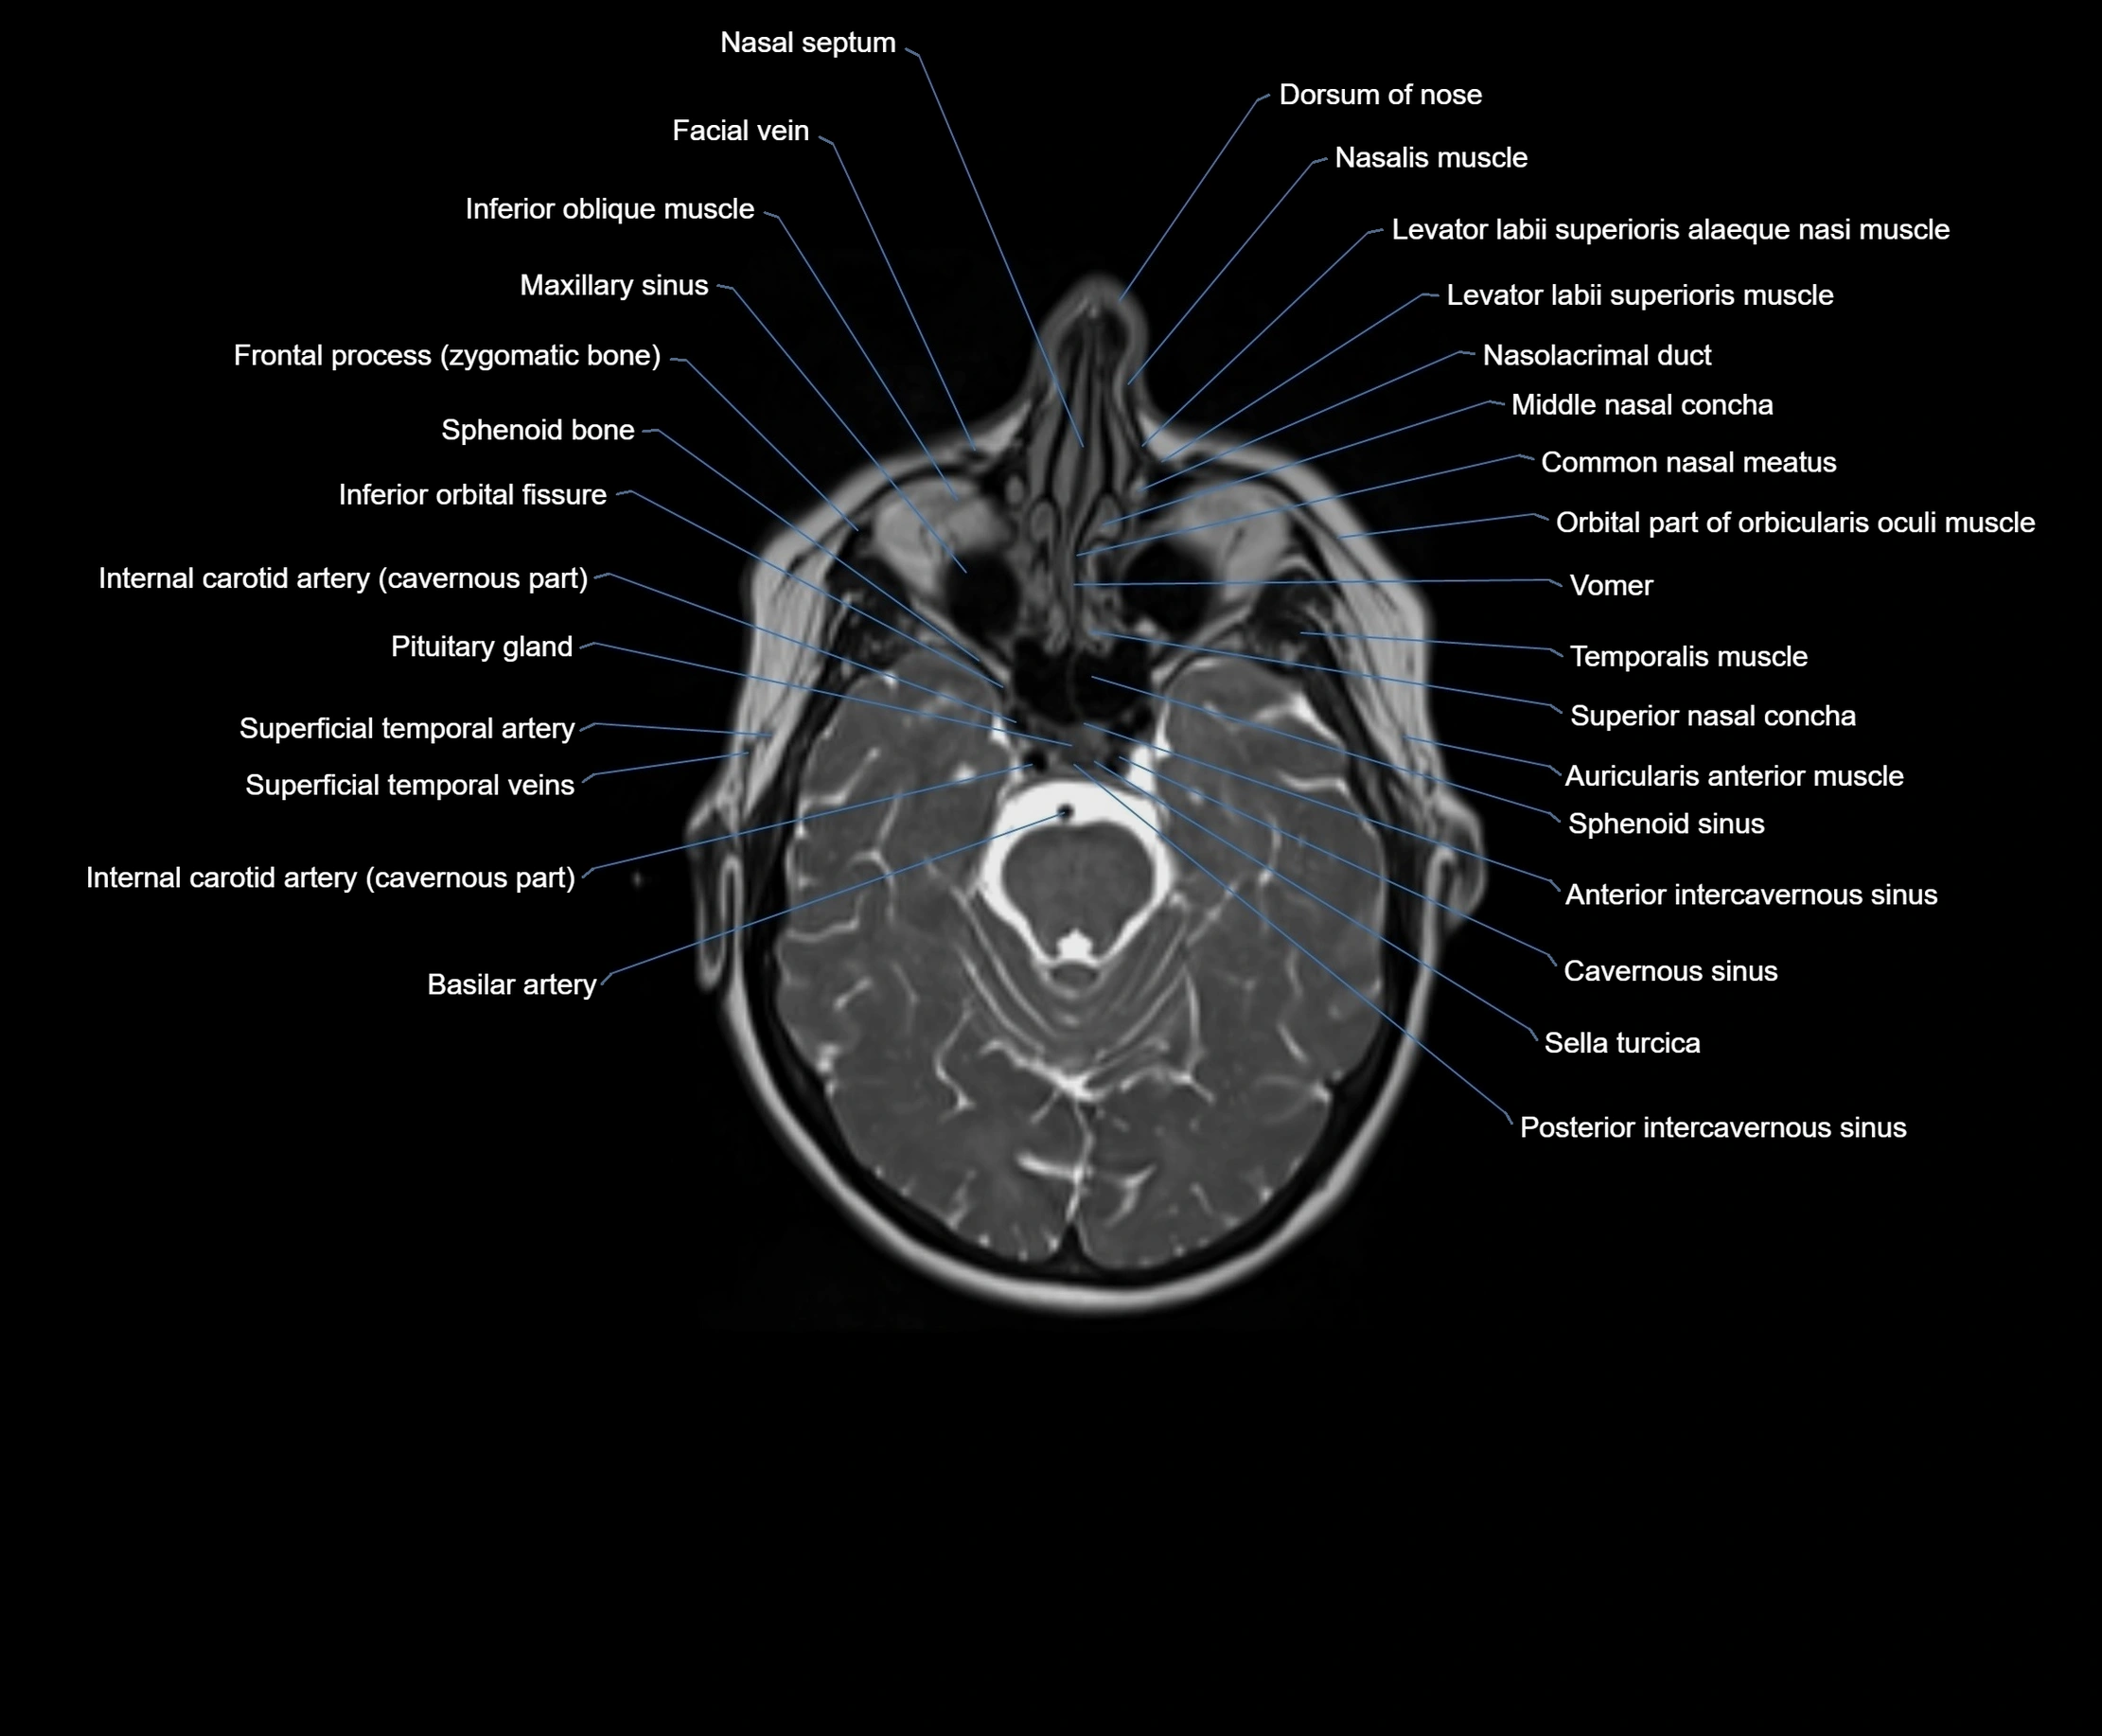

- Common nasal meatus

- Dorsum of nose

- Facial vein

- Frontal process (zygomatic bone)

- Inferior orbital fissure

- Internal carotid artery (cavernous part)

- Middle nasal concha

- Nasal septum

- Nasalis muscle

- Orbital part of orbicularis oculi muscle

- Sella turcica

- Sphenoid sinus

- Superficial temporal artery

- Superficial temporal vein

- Superior nasal concha

- Temporalis muscle

- Vomer